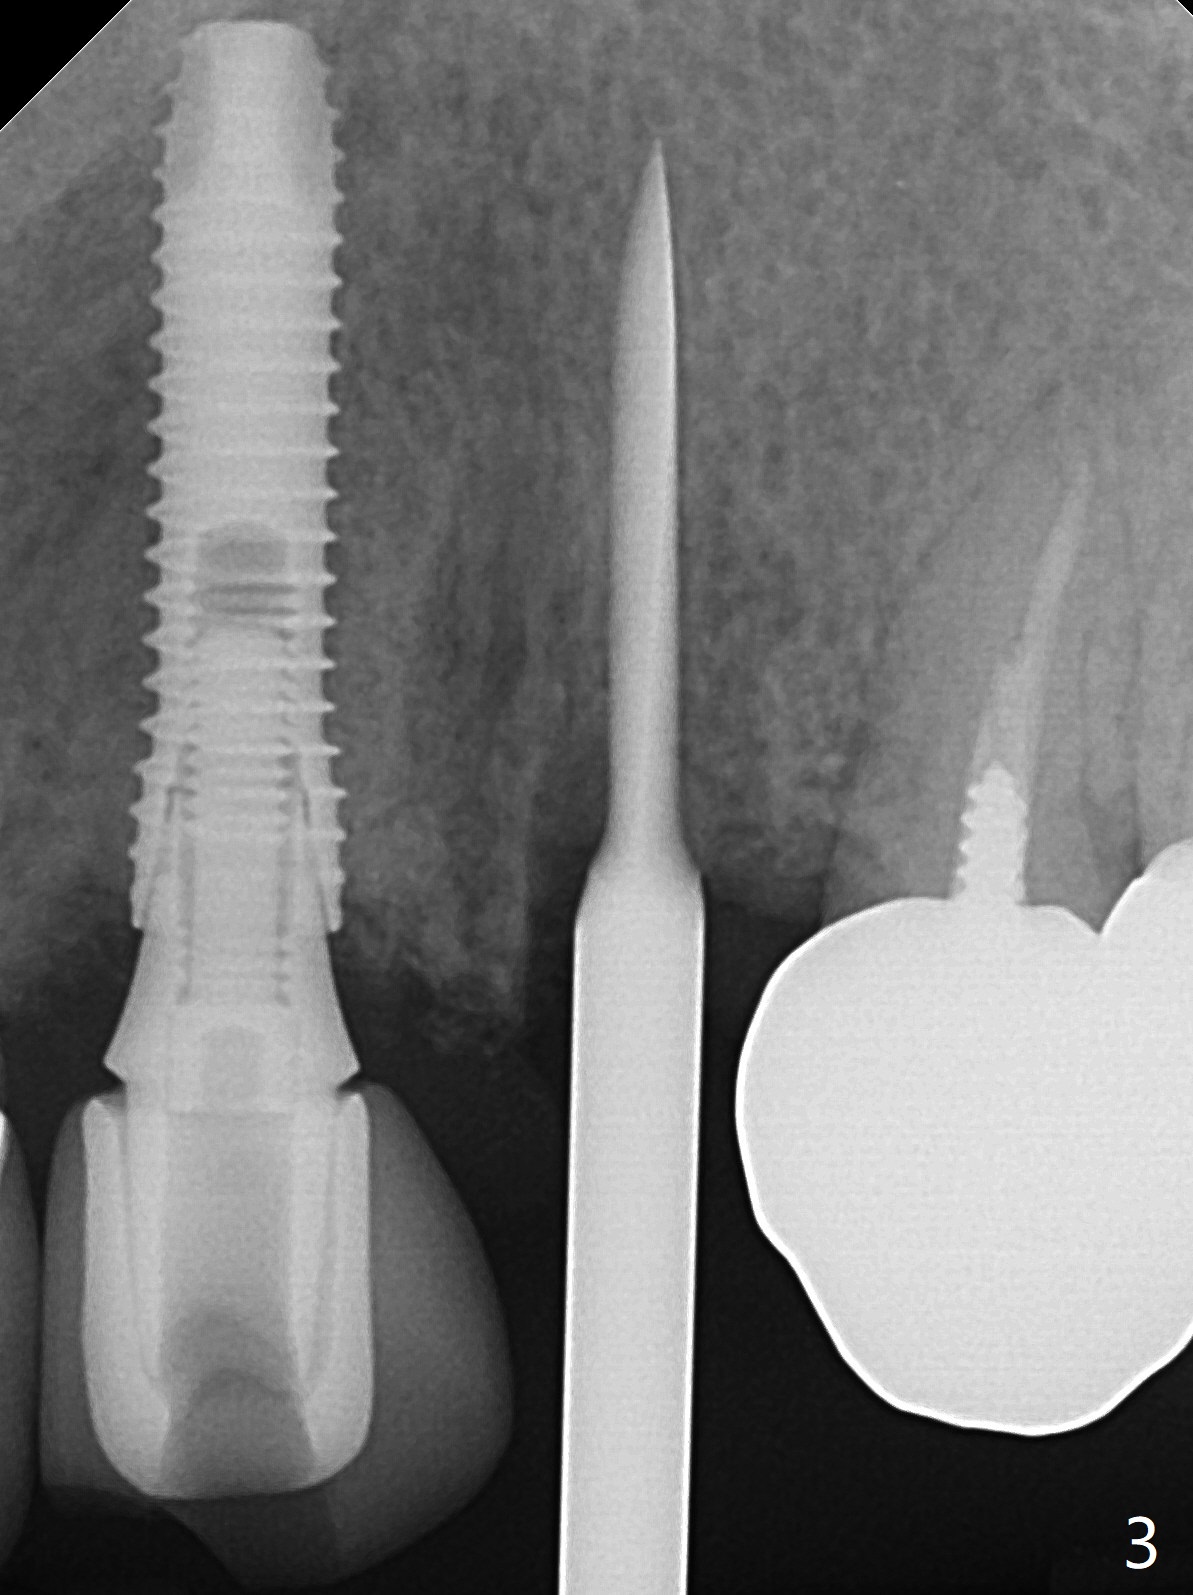

52岁女左上4颊侧牙龈显著肿胀(图一:*(颊侧骨板缺失))伴有瘘道(<),拔除前,在3植牙牙冠切缘舌侧形成开口(图二:*,准备纠正基台不全就位(<);4初步钻洞不正。改变钻头方向后(图三),完成植体放置(图四),并且安置修复基台(4.5x4(2))。磨去3牙冠近中面(图六:*),牙冠和基台反时针旋转(图六:弯箭头),基台完全就位(图四:箭头),调𬌗后,制作4临时牙冠(图六),放置后者前,覆盖半张PRF膜(促进下面粘性骨粉愈合)。图五,六颊侧隆起是因为下面放置许多粘性骨粉。图七是术前CT3D图像(冠状切面),显示颊侧(B),腭侧(P)牙根。拔牙后显示中隔(图八:S),植体植入腭侧窝(图九:绿色),四面骨质包绕,包括中隔;为了修复颊侧骨板,首先放置半张PRF膜(红色)紧贴颊侧骨板腭侧/牙龈,防止骨粉从瘘道流失,然后放置粘性骨粉(图十:粉红色)。术后2.5月3颊侧牙龈仍然红肿(图十一,十二:*),可能与基台袖太短有关(2毫米,图二至四),所以更换袖3毫米的基台(图十三)。术后四个月(牙冠粘固)3颊侧牙龈炎症明显减退(资料没有显示)。术后2.5月4颊侧骨板没有塌陷(图十二,与术后即刻对比(图六))。3基台放置太颊侧,所以在牙冠腭侧制作小的开口(图十四:>),让多余粘固剂流出。取模前3螺丝就拧紧(35Ncm),而4由于有大的开口,粘固后才拧紧(30Ncm)。两个邻牙其中一个可以取出,容易去除另外一个牙冠残余粘固剂。